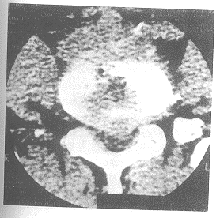

本组优30例(46.15%),良28例(48.57%),可5例(7.69%),差2例(3.08%)。优良率为89.23%(见图1、2)。

图1 治疗前间盘突出

图2 治疗后突出物消失

6.2 关于其治疗机制还待进一步探究,杨克勤及过邦辅在矫形外科学中指出,腰间盘突出引起腰腿痛的原因有三:一是机械性压迫,即突出之间盘组织直接压迫神经根,二是破裂之椎间盘组织释放化学因子所致局部无菌性炎性渗出反应;第三就是免疫作用,认为髓核内含有免疫物质,正常髓核组织是被纤维环封闭的,一旦间盘退变纤维环破裂则此等物质释放入血后即可造成免疫反应。本疗法开展时间短、病例少,初步考虑本药是在后两个环节起到治疗作用,因金葡液含有多种生物活性物质,促进细胞生长因子,可使毛细血管增生,增加血流量,改善微循环,使炎症消退,水肿吸收,痉挛之肌肉缓解,退变破裂的纤维组织修复加上适当的功能锻炼,提高自然治愈力,而达到治疗目的,如例1、2,CT复查突出物已消失,临床治愈。